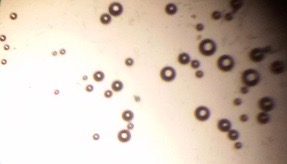

Proniosomes were transformed to noisome by hydrating with 10 ml distilled water at 37 °C and gentle agitation using vortex mixer (MaxiMix II, USA) for 5 min. The formed niosomes were sonicated twice for 30 seconds using sonicator (SONICS VCX 130, USA) [25]. The niosomal dispersion was put on a glass slide, and the formed vesicles were observed at a magnification of 1000x through an optical microscope. The formation of vesicles was observed using an optical microscope and photomicrographs were recorded [26].

The optical photographs of all reconstituted proniosomal formulae are shown in fig. (1-28). The photographs revealed that the formed niosomes are unilamellar vesicles with a spherical shape and smooth surface. The vesicles were insular and separate without aggregation or lumping. Apparently, proniosomal formulae containing span 40 and span 60 yielded vesicles of large numbers with well-identified outline and core which will affect the entrapment efficiency of loaded drug directly. However proniosomal formulae containing span 20 and span 80 produced small numbers of vesicles with a slightly different outline. This may be due to the high phase transition temperatures of both span 40 and span 60 which will cause the formation of a large number of stable niosomal vesicles. The phase transition temperatures for span 20, 40 and 60 are 16, 42 and 53 °C; respectively, however, span 80 possess the lowest phase transition temperature at 12 °C [35]. This explains why proniosomal formulae containing span 20 and span 80 produce small numbers of vesicles upon hydration.